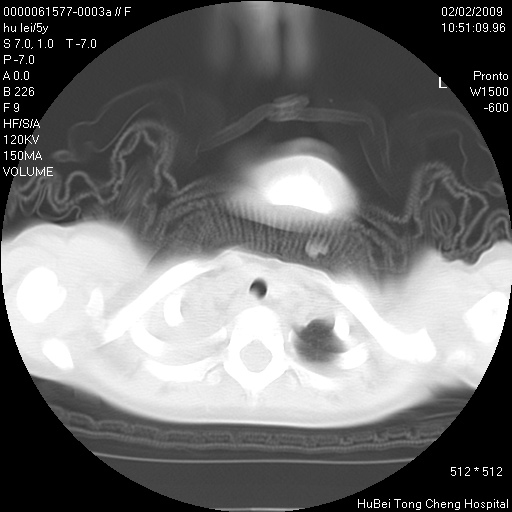

标题: PED1732:M5Y,右肺囊性占位!

患者:男,5。无明显不适,拍胸片考虑右肺囊肿。

行ct扫描,图象如下:

右肺巨大囊肿或包虫

考虑先天性巨大支气管肺囊肿,建议包虫实验除外肺包虫。

右肺巨大囊性占位性病变;考虑巨大肺囊肿,不排除淋巴管瘤可能。

病灶与前胸壁和右上纵隔、叶间裂界限不清,病灶前缘及内侧缘看不到正常的肺组织,不能排除包裹性积液。